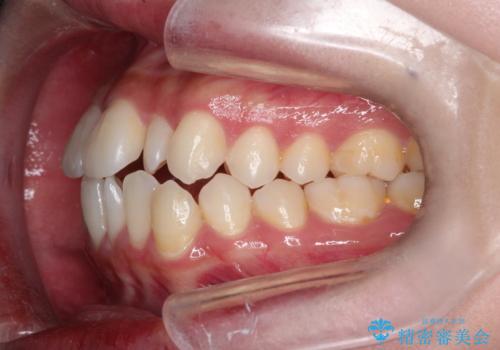

- 口元をさげたいという主訴で来院されました。4番の歯を4本抜歯し、遠心移動とIPRをしました。右上2番が矮小歯のため見た目を重視するならクラウンの提案をしましたが、そのままでの治療を希望されました。

矯正治療の最終段階でスペースクローズにやや時間がかかりましたが、前歯が下がったことで口元の位置も下がりきれいになりました。